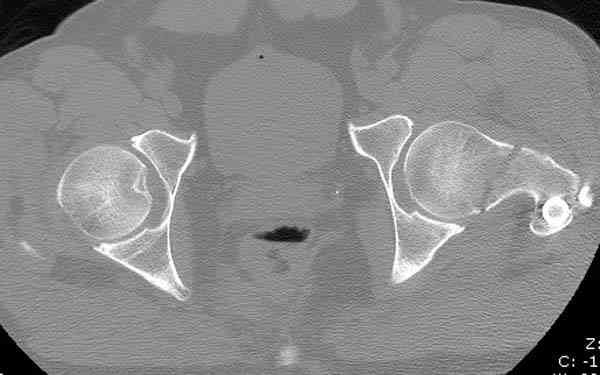

Здесь представлены снимки больного 65 лет, поступившего с диагнозом перелом

бедра после автоаварии.

На второй день (7) обнаружен пропущенный перелом,

сделаны Компьютерная Томограмма